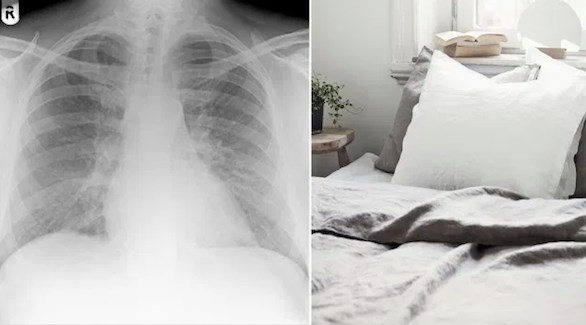

وقد تمت إحالته إلى الدكتور أوين ديمبسي، وهو خبير في طب الجهاز التنفسي بمستشفى فيكتوريا وكيركالدي. هناك، تم تشخيص حالته بالتهاب رئوي ناجم عن فرط الحساسية، وهو رد فعل تحسسي شديد في الرئتين.

وأظهرت الاختبارات أن سبب الالتهاب هو غبار ريش الطيور. وبما أن المريض لم يكن لديه أي اتصال مع الطيور، أدرك الأطباء بأن السبب قد يكون لحافه المحشو بالريش الذي اشتراه قبيل بدء الأعراض لديه.